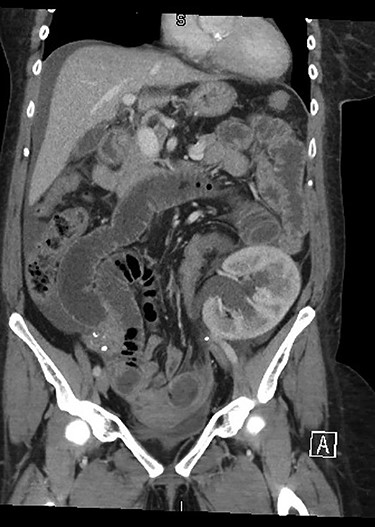

Repeat CT imaging with IV contrast at the referring hospital prior to transfer revealed large volume free fluid intraperitoneally with ongoing dilatation of the renal collecting system which was contrast filled. The distal ureter was not seen entering the bladder. The free fluid in the pelvis also demonstrated increased density raising concern for haematoma or possibly intravenous contrast (Figs 2 and 3).